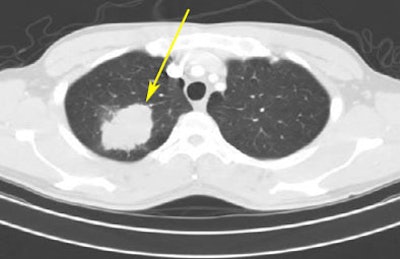

![]() |

| From the RIDER database, a lung cancer case is shown pretreatment (top) and post-treatment (bottom). |